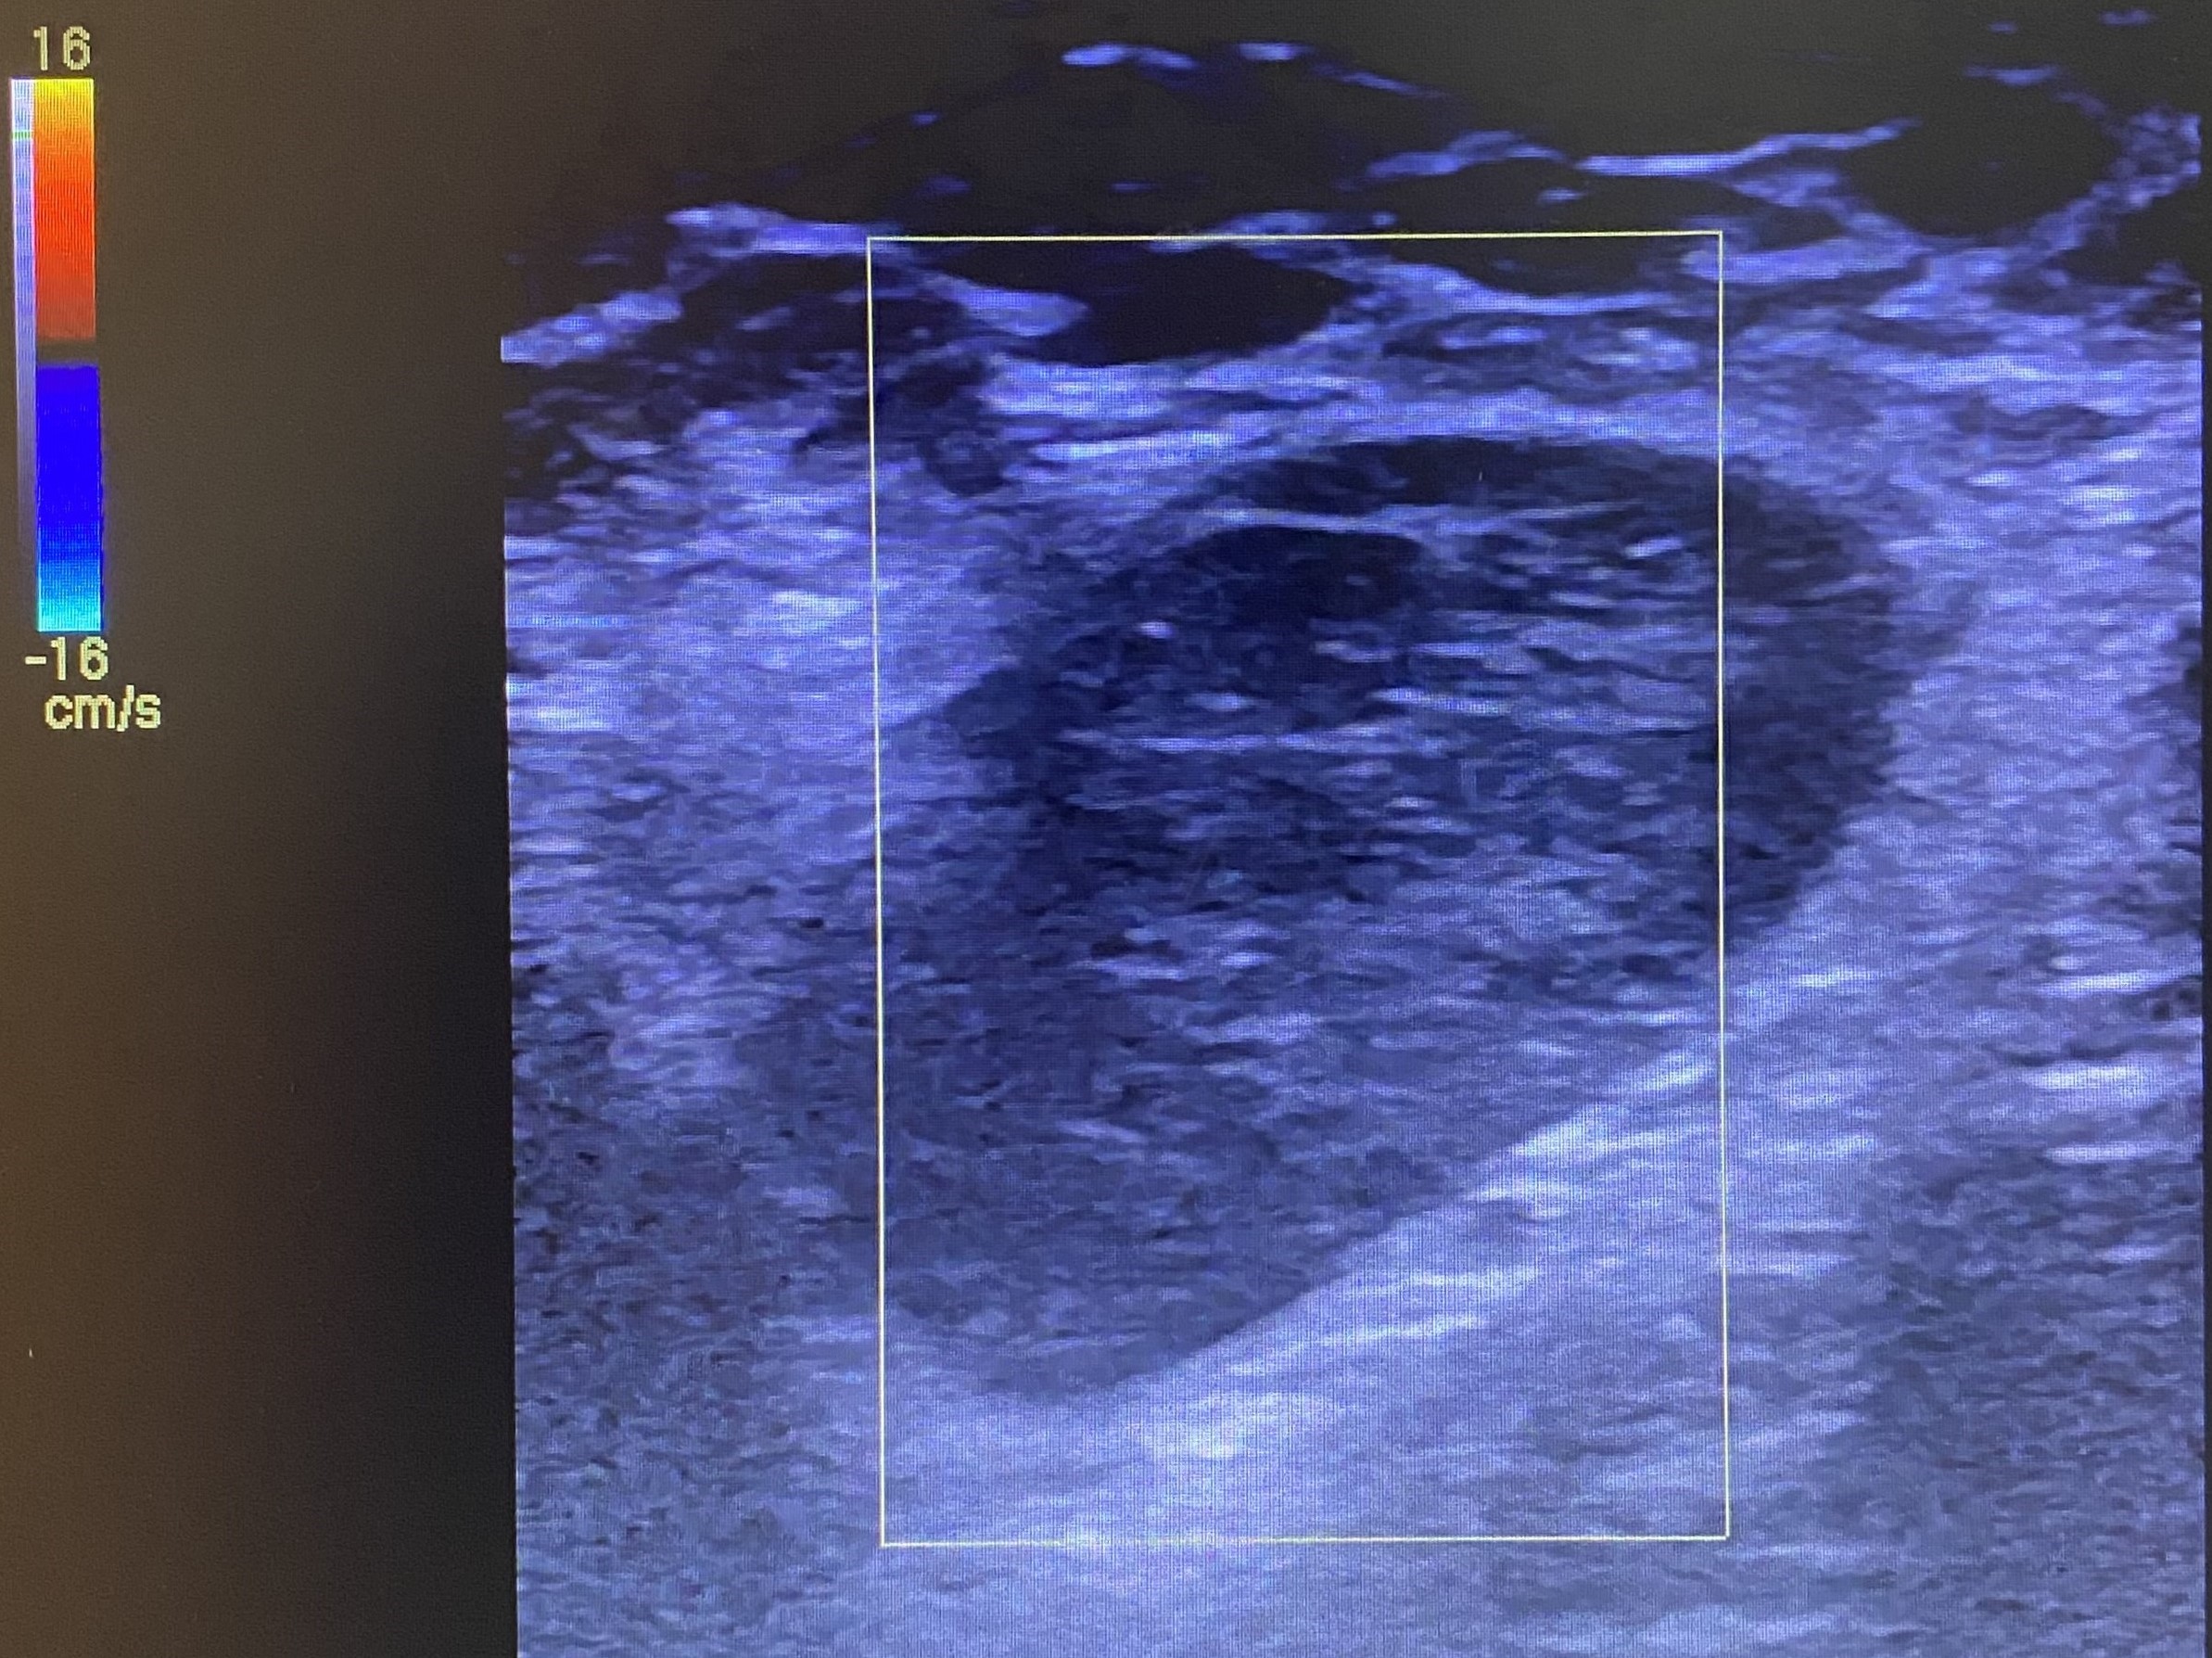

Se realiza una ecografía clínica en la consulta, objetivando múltiples adenopatías axilares izquierdas, la mayor con un tamaño de 2,85 x 1,74 cm. Se observa pérdida de hilio interior y aumento de diámetro transversal. El Doppler color es negativo.